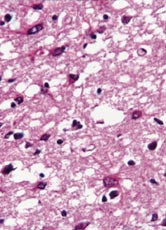

Pasienten. 54 år gammel kvinne. Hun hadde tidligere stort sett vært frisk, men gjennomgikk flere tannekstraksjoner og maksillærkirurgi det siste året før sykdomsdebut. De første symptomene var svimmelhet, asteni og vertigo, som tiltok gradvis. Åtte måneder senere utviklet hun ustø gange, eufori og raskt progredierende demens med desorientering, tap av korttidsminne og visuelle hallusinasjoner. Ved klinisk undersøkelse fant man nystagmus, ataksi, myoklonus, positiv mandibular og palmomental refleks og grav demens. Computertomografi (CT) av hjernen og blodprøver viste normale funn. EEG viste diffus dysrytmi med generalisert theta- og deltaaktivitet, men de typiske periodiske skarpe bølger som vanligvis sees ved Creutzfeldt-Jakobs sykdom, var ikke til stede. T2-vektet MR av hjernen viste ingen definitive avvik (fig 1). Diffusjonsvektet MR av hjernen viste markert økt signaldensitet, dvs. redusert diffusjon bilateralt i corpus striatum og gyrus cinguli (fig 2). Hun døde etter en måned i koma, 15 måneder etter debuten av de første symptomene. Diagnosen ble postmortalt bekreftet med utbredte, typisk spongiforme encefalopatifunn ved den histopatologiske undersøkelsen (fig 3). Prionproteingenanalyse viste ingen mutasjoner, men hun var homozygot for valin/valin i codon 129 (utført ved Creutzfeldt-Jakob Disease Surveillance Unit, Edinburgh, Skottland).

Dette tilfellet av Creutzfeldt-Jakobs sykdom er ett av få hittil rapporterte pasienter (8 – 12) som ble undersøkt med diffusjonsvektet MR. De patologiske forandringene man ser i diffusjonsvektet MR, er tydelige hyperintense signalavvik i basale ganglier og/eller cortex cerebri. Disse forandringene, som representerer redusert diffusjon grunnet funksjonsforstyrrelser i de aktuelle hjernedelene, ser ut til å være karakteristiske for Creutzfeldt-Jakobs sykdom. Det finnes ikke andre rapporterte tilstander med liknende diffusjonsforandringer. Diffusjonsvektet MR kan derfor være en undersøkelse som gir spesifikke funn for Creutzfeldt-Jakobs sykdom, og et nytt instrument i den premortale diagnostikken av denne sykdommen.